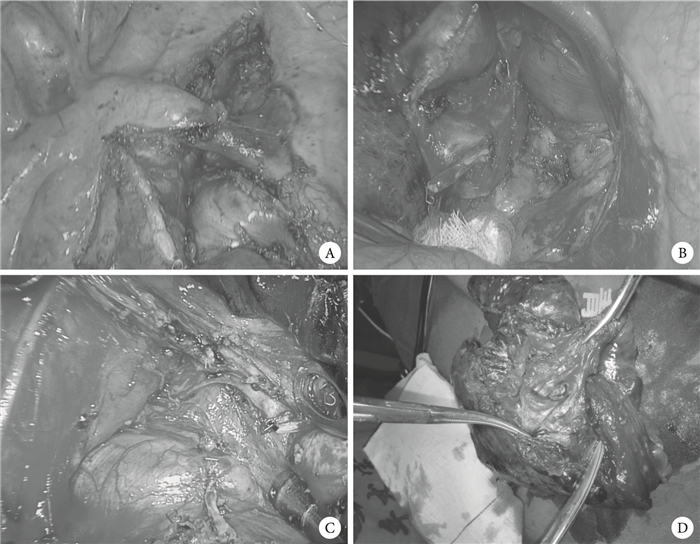

兩組患者均行解剖式肺葉切除及肺門、縱隔淋巴結R0清掃術。肺葉切除時,若患者肺裂發育較好,處理順序一般按照靜脈、動脈、支氣管;若患者肺裂發育不全,處理順序一般按照靜脈、支氣管、動脈,其中在單孔組中,因上葉手術難度較大,一般順序會改為尖前支、靜脈、后升支及支氣管。動脈、靜脈、支氣管及不完全肺裂均由同一型號切割閉合器閉合。淋巴結清掃時,兩組患者肺門、縱隔淋巴結清掃數目及站數均按統一標準,右側第2、4、5、6、7、8、9、10、11、12組,左側第4、5、6、7、8、9、10、11、12組。我們定義淋巴結清掃術為“裸化”清掃,見圖 1。

注: A 為右側上縱隔淋巴結清掃; B 為左側隆突下淋巴結清掃; C 為右側隆突下淋巴結清掃; D 為 12 組淋巴結清掃